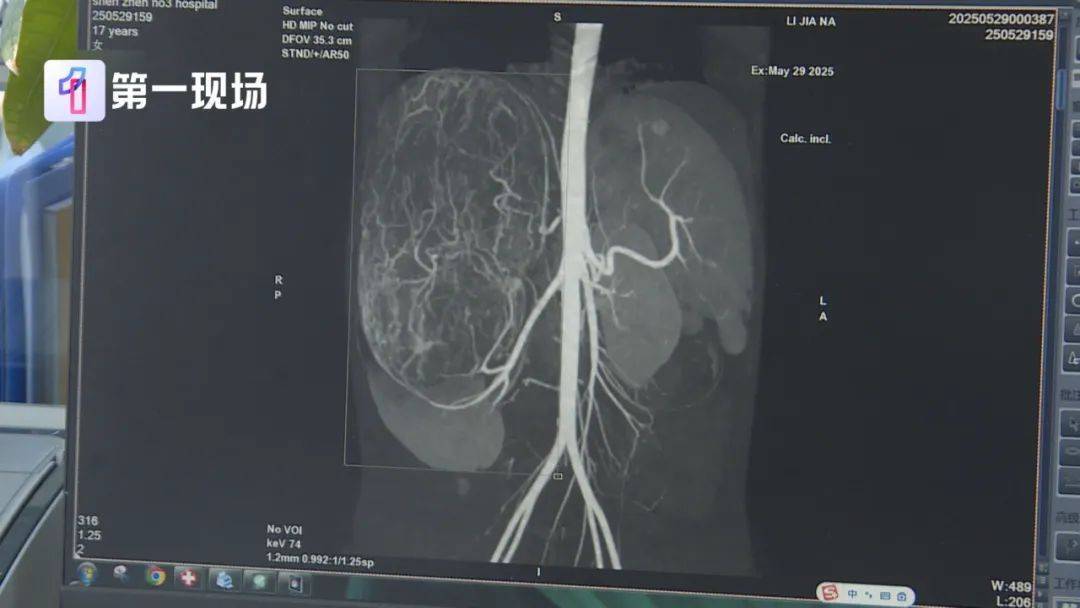

广东17岁女孩婷婷(化名) 今年读高二 前段时间 妈妈带着她去逛街买衣服 试裤子的时候店员来帮忙 感觉孩子身形消瘦 但肚子却有点大 于是建议妈妈带她去医院看看 结果一查吓一跳 婷婷的肚子里 竟然长了一